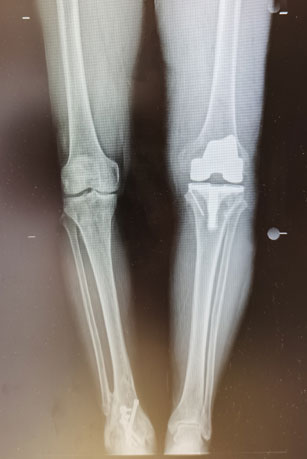

王兴龙为患者进行了详细查体,完善了相关检查,发现患者膝关节内翻畸形达25度,并伴有近20度的屈曲挛缩畸形,手术难度极大。手术可能需要特殊关节假体,但此类假体费用非常昂贵。为了以最经济的方法获得同样的疗效,王兴龙通过术前仔细测量、规划,决定为患者应用普通关节假体进行手术。术中,患者膝关节异常僵硬,软组织松解、平衡困难,截骨后胫骨侧伴有较大的骨缺损。由于术前准备充分,通过袖套样松解、拉花技术、胫骨平台缩小、应用水泥螺钉技术,手术难点被一一攻克。在麻醉科、手术室和关节团队的密切配合下,手术顺利完成。术后,我院康复医学科为患者进行个性化的康复治疗,术后第五天,患者康复出院。